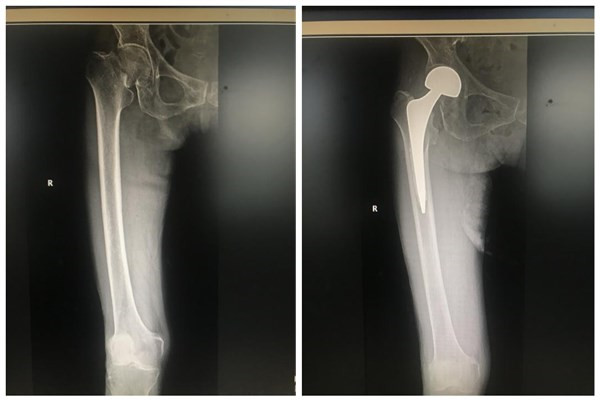

83岁老太太右股骨颈骨折术前术后影像资料

另一例是83岁老太太,今年5月不慎摔倒由家属送到我院骨科一病区救治,诊断为右股骨颈骨折,移位严重,不行手术死亡率极高,家人曾认为老人家年纪大了,担心手术风险和手术技术是否成熟,术后恢复怎样,曾经想放弃手术。科室为患者制定详细的手术计划及围手术期周密准备,给予行右髋人工股骨头置换手术,手术成功,术后2天老人可下床活动。现在去看望老人家已能不用拐杖自行行走了,恢复到原来正常的生活状态,生活能自理,患者及家属非常满意。